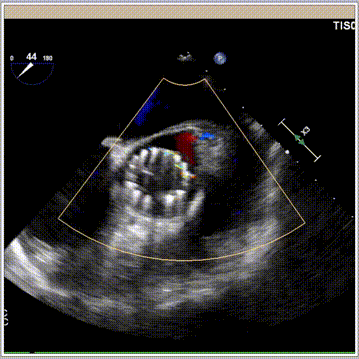

术前心超提示

主动脉瓣钙化伴重度狭窄,Type 0型二叶瓣,升主动脉增宽,左室壁增厚,二尖瓣轻度反流,三尖瓣轻中度反流,左实验室舒张功能减退。LVEF:73%,CW估测跨瓣峰值流速约为Vmax:5.62m/s,平均压差约 75mmHg ,AVA 0.73cm²。

术后心超